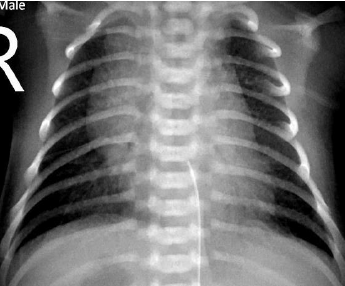

Lactente de 1 mês de vida chega para atendimento. Ao exame físico, está acianótico, não é auscultado sopro cardíaco e os pulsos são simétricos nos 4 membros. Considerando o seguinte raio-x, o que é mais esperado encontrar nesse paciente?

Provas